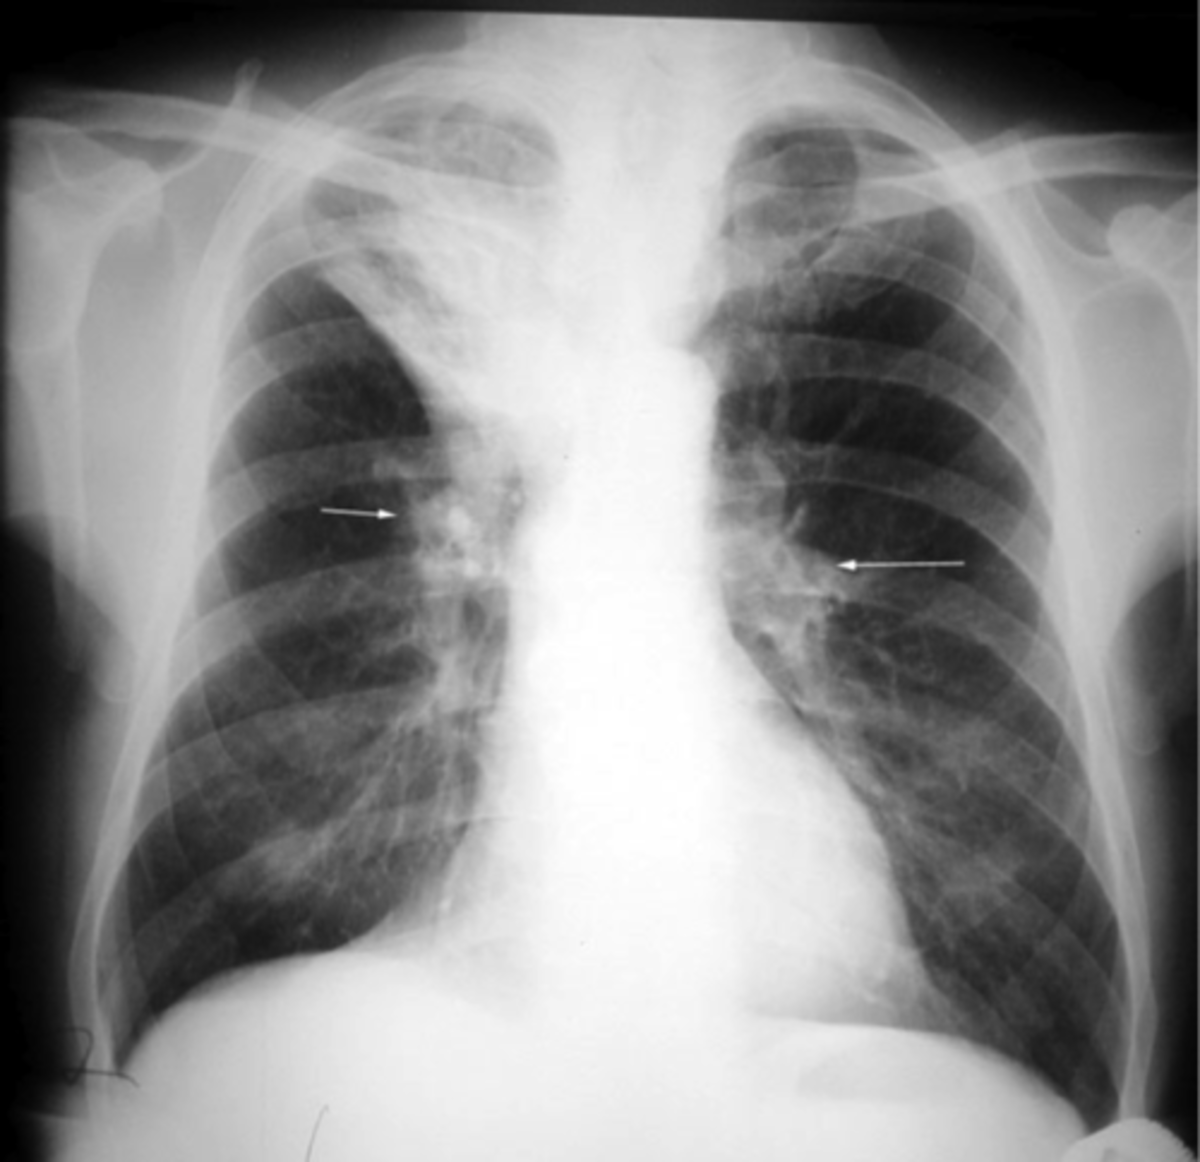

Chest Xray of patient 1 at admission atelectasis in the left lower

Chest Xray of patient 1 at admission atelectasis in the left lower Atelectasis Cause Chest X-Ray In most cases affecting adults, atelectasis will appear in the lower left lobe of the lungs. But other tests may be done to. If imaging is warranted, chest radiography, chest computed tomography, or thoracic ultrasonography are useful when diagnosing. Common etiologies include granulomatous disease, necrotizing pneumonia and radiation fibrosis. Atelectasis is a radiopathological sign that can be categorized in many. Atelectasis Cause Chest X-Ray.